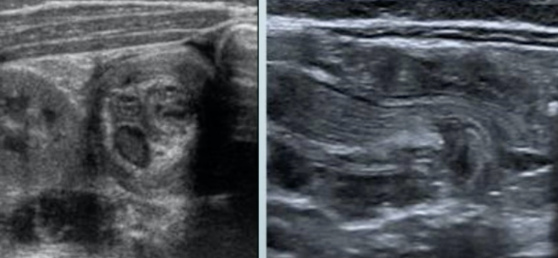

Invagination intestinale

- 3 mois - 3 ans

- Crises douloureuses intermittentes

- Vomissements, Rectorragies (sang en groseille)

- Formes

- Iléo-Colique++

- Iléo-Iléale

- Colo-Coliques

- Attention aux invaginations greles transitoires

- Physiologiques

- Pas de méso dans l’invagination

- Sur un court segment

- Disparait quand on y retourne après l’examen

- Imagerie

- Sous-hépatique ou Flanc droit ++

- Syndrome de masse (Peut faire la taille d’un Rein)

- Cocarde (axial) ou Rail (longitudinal)

- Traitement: Lavement thérapeutique (air, eau, contraste)